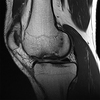

Figure 1 is the MRI scan of a 15-year-old boy who has had knee pain with running for 5 months. What is the most appropriate treatment?

Arthroscopic or open reduction and internal fixation ## Footnote OCD is an acquired lesion of the subchondral bone. Patients with OCD initially report nonspecific pain and variable amounts of swelling. **Initial radiographs help identify the lesion and establish the status of the physes**. An MRI scan is useful for assessing the potential for the lesion to heal with nonsurgical treatment. **Nonsurgical treatment is appropriate for small, stable lesions in patients with open physes and focuses on activity restriction for 3 to 9 months**. Surgical treatment is necessary for unstable or detached lesions. Stable lesions with intact articular cartilage can be treated with subchondral drilling to stimulate vascular ingrowth, with radiographic healing at an average of 4.4 months. Fixation is indicated for unstable or hinged lesions, and stabilization of the fragment can be achieved using a variety of implants through an arthroscopic or open approach. The fragment should be salvaged and the normal articular surface restored whenever possible.